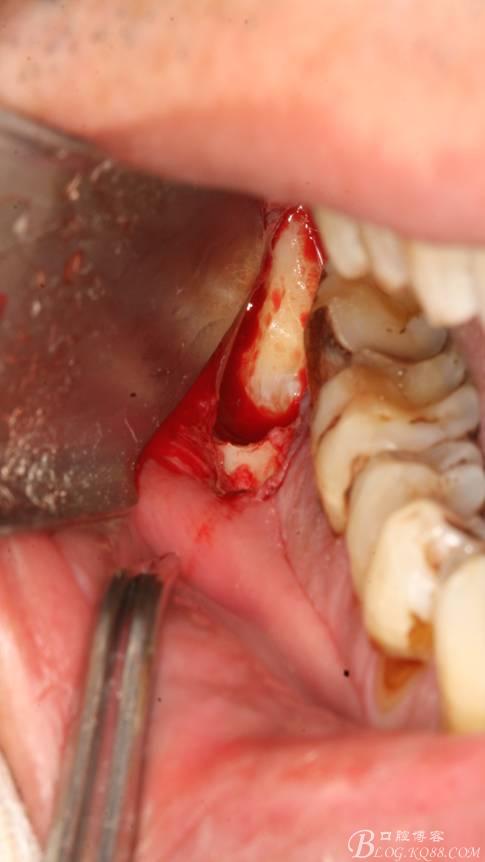

4. 縱分牙根和牙冠

5.取出牙根